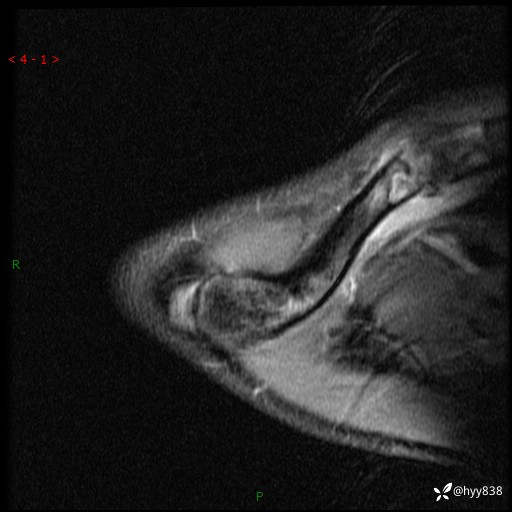

MRI(cor T1WI+T2WIfs+axi T2WIfs)